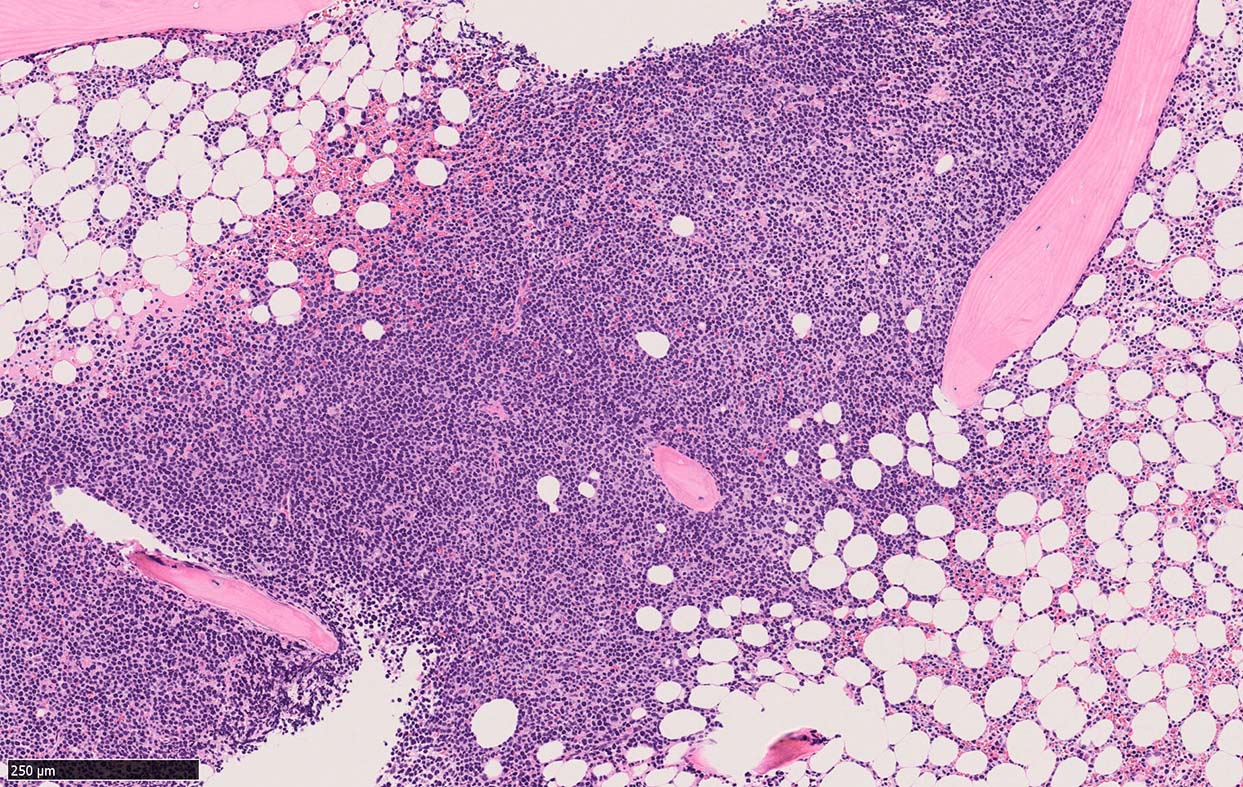

Bone marrow involvement of mantle cell lymphomaの症例

骨髄骨梁間に密なASD-Giemsa陰性の小型~中型円形細胞の浸潤が認められる.

MCLは60-90%の症例で骨髄に浸潤する. *1*2*3*4*5. 骨髄浸潤の最も一般的なパターンは, focal random(限局性, ランダム)で, 80%以上の症例でみられる.

骨梁間(interstitial)には約50%, びまん性浸潤は20~30%の症例でみられる。*1,*6 とくに, 傍骨梁浸潤は45%の症例に認められる. 時には、濾胞性リンパ腫に似た傍骨梁のみの浸潤を認めることもある. まれに、顕著な類同内浸潤を伴う症例も報告されている。*7